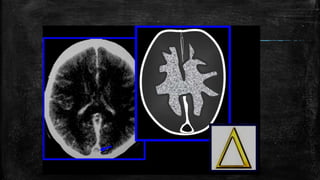

• #92 Moya moya appearance. Lateral anterior oblique view (A) of an internal carotid artery (thick short arrow) angiogram shows multiple, small, tortuous collateral vessels in the distribution of the middle cerebral artery (arrows), suggestive of the moya moya (puff of smoke) appearance. Axial view of the MRI angiogram (B) shows complete occlusion of the middle cerebral arteries bilaterally. Arrows indicate the internal carotid arteries